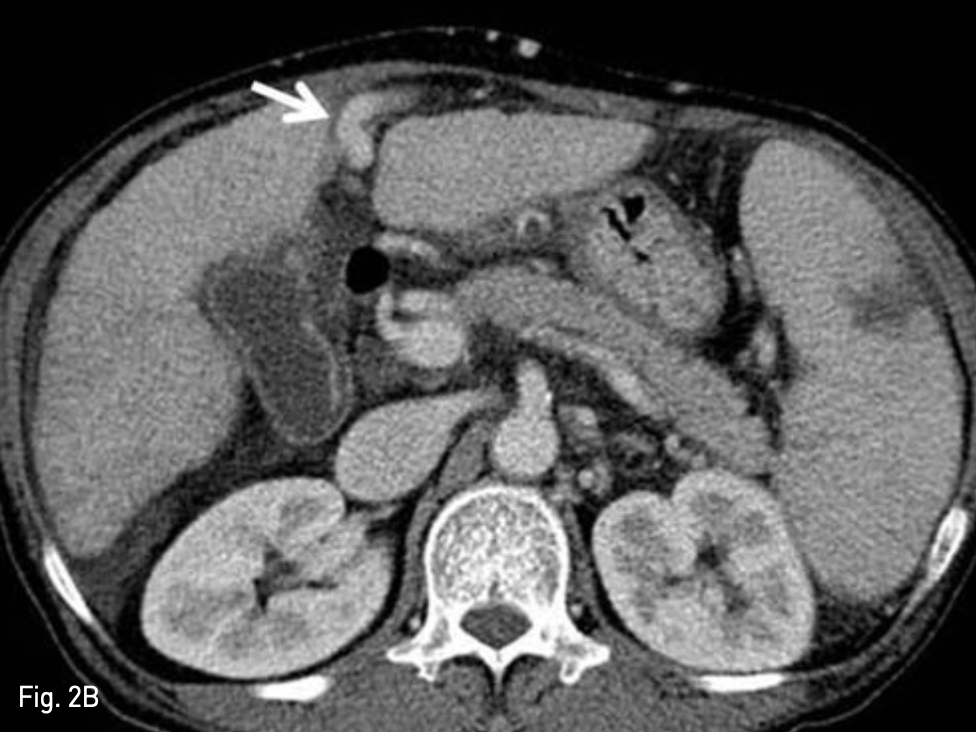

Fig. 2

Liver dynamic CT for preprocedural evaluation

A. Venous phase CT image revealed dilated recan alized paraumbilical vein in abdominal wall (arrow)

B. This recan alized paraumbilical vein drains left portal vein (arrow).